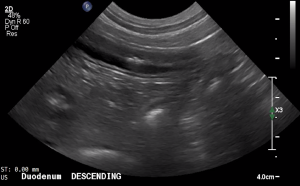

SIMON Ultrasound Database

This ultrasound database is a free resource for students and doctors!

Our collection includes videos of dogs, cats, horses, cows, humans, and many other species!